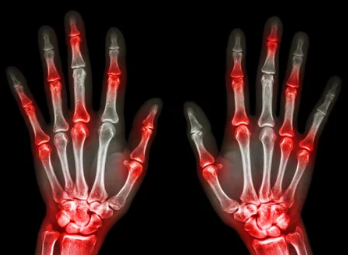

통풍 초기 증상을 방치하면 만성 통풍으로 진행될 수 있습니다. 만성 통풍은 관절 변형, 신장 기능 저하, 요로 결석 등 심각한 합병증을 유발할 수 있습니다. 따라서 통풍 초기 증상이 의심된다면 즉시 병원을 방문하여 정확한 진단과 치료를 받는 것이 중요합니다.

통풍 초기 증상이 의심된다면 류마티스내과 전문의를 찾아 정확한 진단과 치료를 받는 것이 중요합니다. 혈액 검사, 관절액 검사, X-ray 검사 등을 통해 통풍 여부를 확인하고, 약물 치료, 식이요법, 운동 요법 등을 통해 통증을 완화하고 재발을 방지할 수 있습니다.